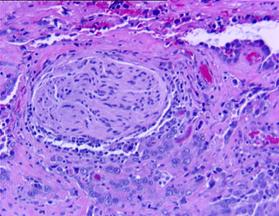

Fig.3 Carcinom in situ (HEx10) [51].

a) b)

Fig.6 Aspecte microscopice. a) Carcinom urotelial cu grad inalt de malignitate (Hex10) b) Invazie tumorala in intesitiile muscularei propii. (Hex5). [51].